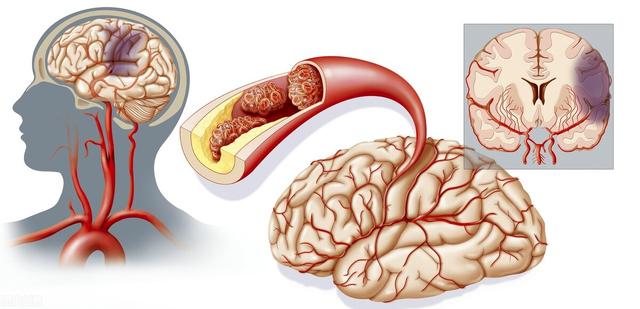

第6 脳血管障害によるもの

特に高齢者では、片腕のしびれや手指のしびれ、手足の脱力を伴う場合には、脳血管障害の発生に注意する必要がある。

4.脳血管疾患

脳血管障害の前駆症状であれ、すでに発症した後の症状であれ、脳血管障害のリスクが高い人にとって、指のしびれは特に注意すべき症状の一つであると言える。ただし、脳血管障害による手指のしびれは、他の症状を伴うことが多く、単独の症状として手指のしびれがみられることもまれではないことを指摘しておく。

まず、脳血管疾患は、指のしびれが原因の脳血管疾患に対して、虚血性脳血管疾患であれば、患者に血行を改善させるだけでなく、栄養神経治療を行うことができ、一般的に患者にイチョウ葉製剤やメチルコバラミン製剤を与えることができます。脳血管障害の急性期であれば、鍼灸治療や漢方薬のイオン導入療法を行うこともできます。

主な問題は、小さな脳梗塞、腫瘍の圧迫、頭蓋内血管奇形の圧迫などである。

指のしびれの主な原因はいくつかある。

一過性脳虚血は手指のしびれの原因として高齢者に多く、特に片側の手足のしびれがある場合に注意が必要である。一過性脳虚血の原因と病態は、脳動脈壁の微小塞栓、脳動脈狭窄に基づく血圧低下、脳血管攣縮などである。上記のような症状が出現した場合には、時間内に病院を受診し、高血圧、高脂血症、高血糖、心房細動などの脳血管障害の危険因子を総合的にスクリーニングし、積極的な予防と治療を行う必要がある。

- もしそうなら指のしびれが頻繁にある人は、40歳以上の中高年に多い脳卒中に注意する必要がある。指のしびれだけでなく、次のような症状もしばしば見られる。頭痛、めまい、ふらつき、舌の腫れなど。..糖尿病患者は高血糖を持っており、高血糖は体の麻痺を引き起こす可能性があり、手や足がしびれが表示されます、それは血糖値の監視のために病院に行くことをお勧めします、あまりにも高い場合は、治療のコントロールをスピードアップする必要があります。

- 高血圧や高コレステロールなどの病気は、血管攣縮や血管の硬化を引き起こすことがある。同時に、高齢者の血液の粘度が高い方なので、一過性の脳虚血を起こしやすく、その結果、指がしびれる。頚椎の肥大・過形成や頚椎椎間板の変性・突出などにより、頚神経根や頚髄が圧迫されるため、片側または両側の手指のしびれや痛み、右手指のしびれや痛み、さらには上肢の活動障害を引き起こし、時には腕全体から肩にかけてのしびれや痛みに耐えられず、ペンを持ったり、ジャンパーを編んだりすることが困難になります。

6.脳梗塞

この病気は、現在、中高年に比較的多い病気で、上肢や手指のしびれが出現することもあり、その原因は、頸動脈圧迫、動脈硬化、脳血栓症などが原因で、脳組織が虚血・低酸素状態になるため、脳神経が障害され、上肢を支配する神経に異常が出現し、それにつながる。